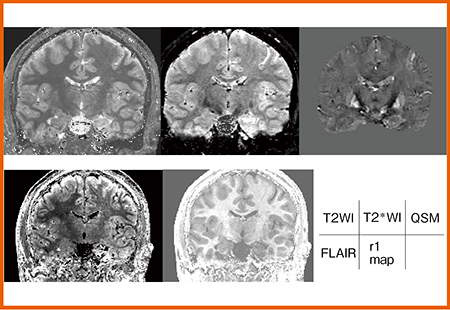

また,磁化率画像(QSM)も作成可能で,GRE法のT2*強調画像と同じように,QPMのT2*強調画像でもプラーク部分に高信号が認められる(図3 a)。また,QSMの高信号は磁化率の増加を反映することから,出血の存在も疑われる(図3 b)。

図3 症例1:QPMによる磁化率画像

QPM(図5)では,T2強調画像とT2*強調画像で左側海馬に軽度の信号変化を認める。一方,FLAIR画像では同部に明らかな高信号,r1マップでは側頭葉内側から下部にかけて明瞭に低信号が認められた。また,ミエリンマップでも海馬付近に低信号が認められ,髄鞘の低下が示唆された(図6 a)。側頭極レベルではさらに信号が低下し,左側のミエリン密度の低下と菲薄化が確認できた(図6 b)。FDG-PETでも,左側皮質側にFDG集積の低下,アシンメトリーマップでもFDG低下が確認できたことから,QPMは神経変性を表していると考えられる。

図5 症例2:QPMによる各種パラメータ画像